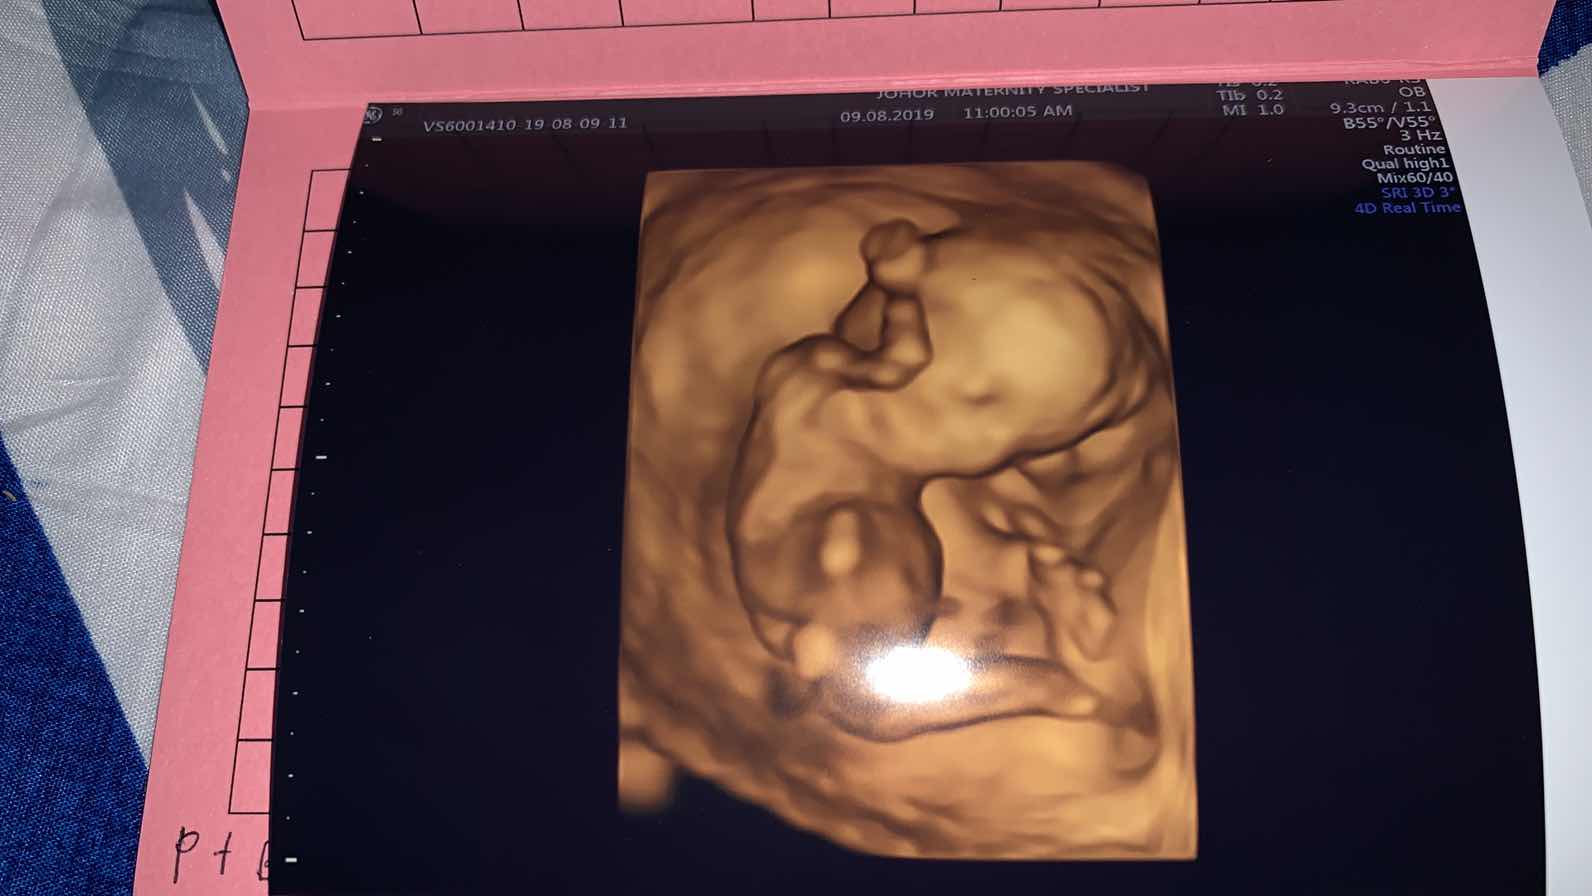

Baby mama 14 week 1 day,mse doc scan aktif dia brgerak,doc tu ckp da taw blum jamtina baby? Blum doc,nk taw x?nk2..dr trus ckp ni baby girl,alhamdulillah mama happy sgt2,Doc ni memg bgs,mse mama smpai johor maternity kluang ni rmai sgt org nk jumpe dye,mama dtg pkul 7.20 pagi dpt giliran 25..x expect dpt jumpe doc ni,main pi je,yg igtkn dpt print 2d scan skli dia bg 4d,hrge rm65 skli bkak buku..alhamdulillah rzeki baby mama..mommy2 sume doakan baby sy sihat sntiase ye,sy doakn mge mommy n baby2 mommy sihat sntiasa aminn